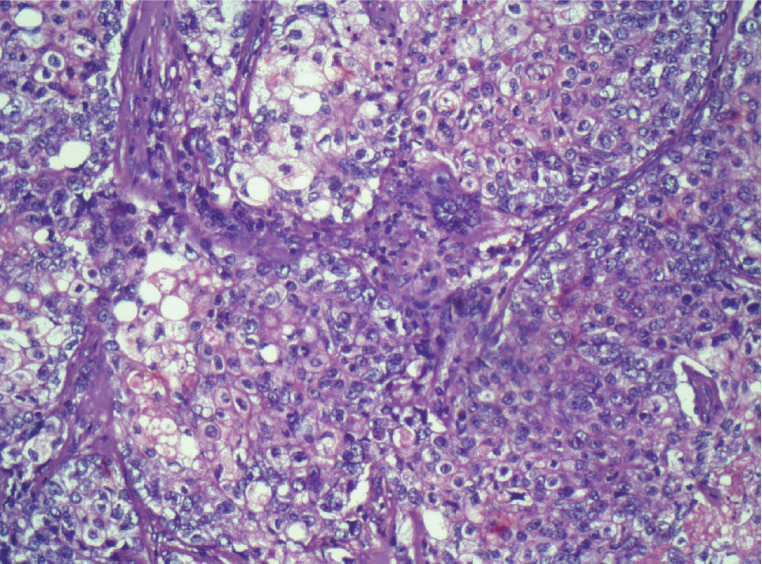

Background: Sebaceous carcinoma of the breast (SCB) is an unusual neoplasm. To the best of our knowledge, only 30 cases have been reported in the literature. Due to its rarity, there is limited knowledge on how to manage patients with SCB. This article aims to describe a case of multicentric sebaceous breast carcinoma in a 33-year-old woman detailing the diagnostic process, historical findings and the treatment approach.

Abstract Image